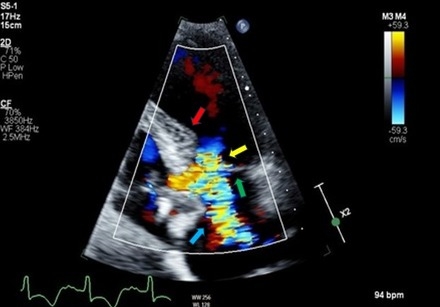

Case: A 76-year-old female presented with typical chest pain, nausea, and worsening shortness of breath. On examination, she was hypotensive and cold to touch. EKG showed T-wave inversions in lateral leads with elevated cardiac troponins. Coronary angiogram showed non-obstructive coronary artery disease, and right heart catheterization revealed elevated filling pressures. Transthoracic echocardiogram (TTE) showed septal hypertrophy and SAM of the mitral valve causing dynamic LVOT obstruction (Figure 1) and ejection fraction (EF) of 20%. TTE with contrast showed apical ballooning consistent with TC (Figure 2).